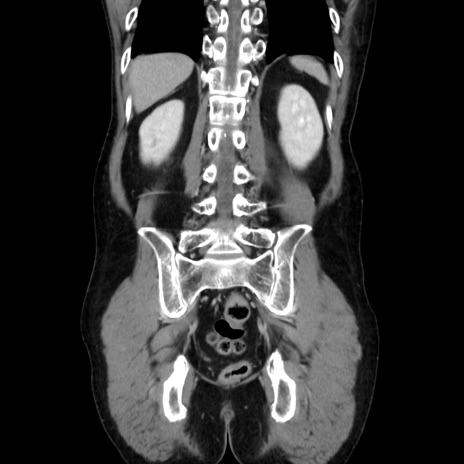

症例37(冠状断像)

【症例】40歳代 男性

【主訴】腹痛

【現病歴】4時間ほど前に電車に乗車中に臍部上より腹痛出現。徐々に増悪し起立困難となり、救急外来受診。生ものは数日食べていない。今朝お雑煮を食べた。

【身体所見】BT 36.8℃、BP 117/84mmHg、HR 91/min、SpO2 97%、苦悶様、腹部:臍上部広範囲圧痛あり、反跳痛±

【データ】WBC 8100、CRP 0.03